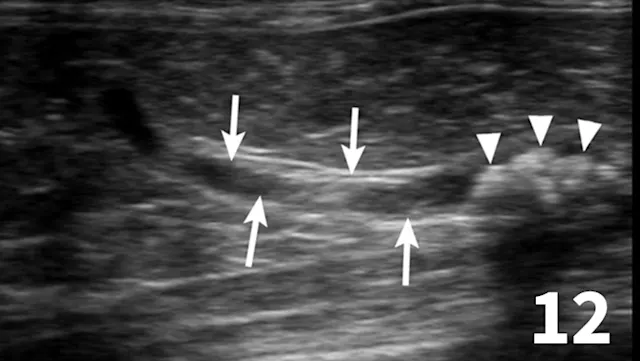

Normal ureters cannot be visualized with survey radiography or ultrasonography, but normal and abnormal ureters are readily visualized with excretory urography. The location of a ureteral obstruction or rupture as well as the presence of an ectopic ureter (especially when combined with pneumocystography) can be documented with excretory urography (Figure 11). A dilated ureter (hydroureter) can be observed with ultrasonography (Figure 12). Pyelocentesis (for cytology and culture) and antegrade pyelography (nephropyelography) (Figure 13) to document obstruction or leakage can be conducted via ultrasound guidance with heavy sedation or anesthesia. Ultrasonography can also be used to visualize retroperitoneal fluid accumulation, which may occur with a ureteral rupture, hemorrhage, or infectious or neoplastic disease. Whereas ureteroliths without hydroureter may be missed on ultrasonography, radiopaque ureteroliths can be observed on survey radiography (Figure 14). Survey radiographic visualization of radiopaque ureteroliths may be facilitated by enemas to empty the colon of fecal material and/or use of a radiolucent paddle to apply regional compression over the ureter to separate adjacent organs (eg, loops of bowel) (Figure 15). Aged cats with chronic kidney disease (CKD) frequently have calcium oxalate nephroliths; in some cases, these nephroliths will migrate into the ureters. Survey radiographs should be employed to rule out ureterolithiasis, especially in cats with acute decompensation of their CKD (Figure 16).